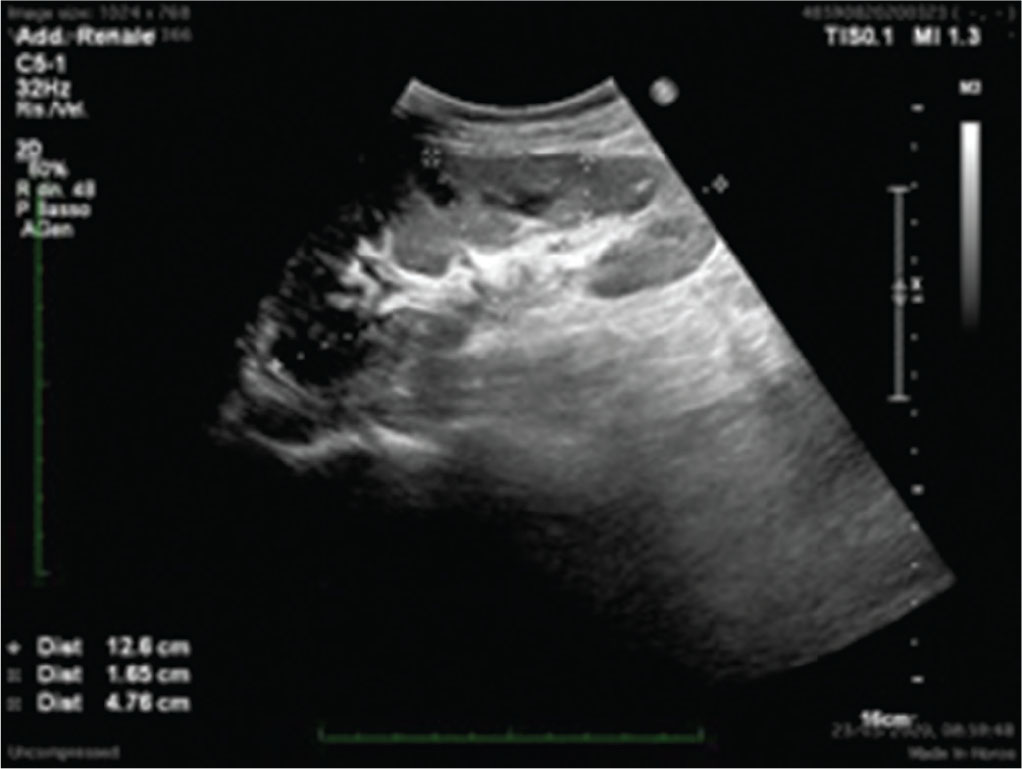

Dal punto di vista morfostrutturale, il rene trapiantato appare molto simile a quello nativo, anche se l’assenza della capsula adiposa perirenale e la sua posizione molto superficiale potrebbero modificarne leggermente le caratteristiche ecogeniche (Fig. 1).

Anche le sue dimensioni sono simili a quelle dei reni nativi, anche se, progressivamente, tendono a incrementarsi per i processi di iperfiltrazione. Il parenchima renale e la differenziazione cortico-midollare sono solitamente ben visibili e caratterizzabili. Il sistema collettore di un TR ben funzionante può apparire lievemente dilatato, anche in relazione alla presenza dello stent ureterale JJ, ben visibile ecograficamente grazie alla sua immagine a doppio binario lineare che termina, da una parte, nella pelvi renale e, dall’altra, in vescica. In aggiunta, l’elevata quantità di urina che scorre nelle vie urinarie principali e la perdita di tonicità ureterale derivata dalla sua denervazione sono fattori potenzialmente favorenti lo sviluppo di idronefrosi moderata.

(Personal image, Fondazione IRCCS Ca’ Granda Ospedale Maggiore Policlinico, Milano)